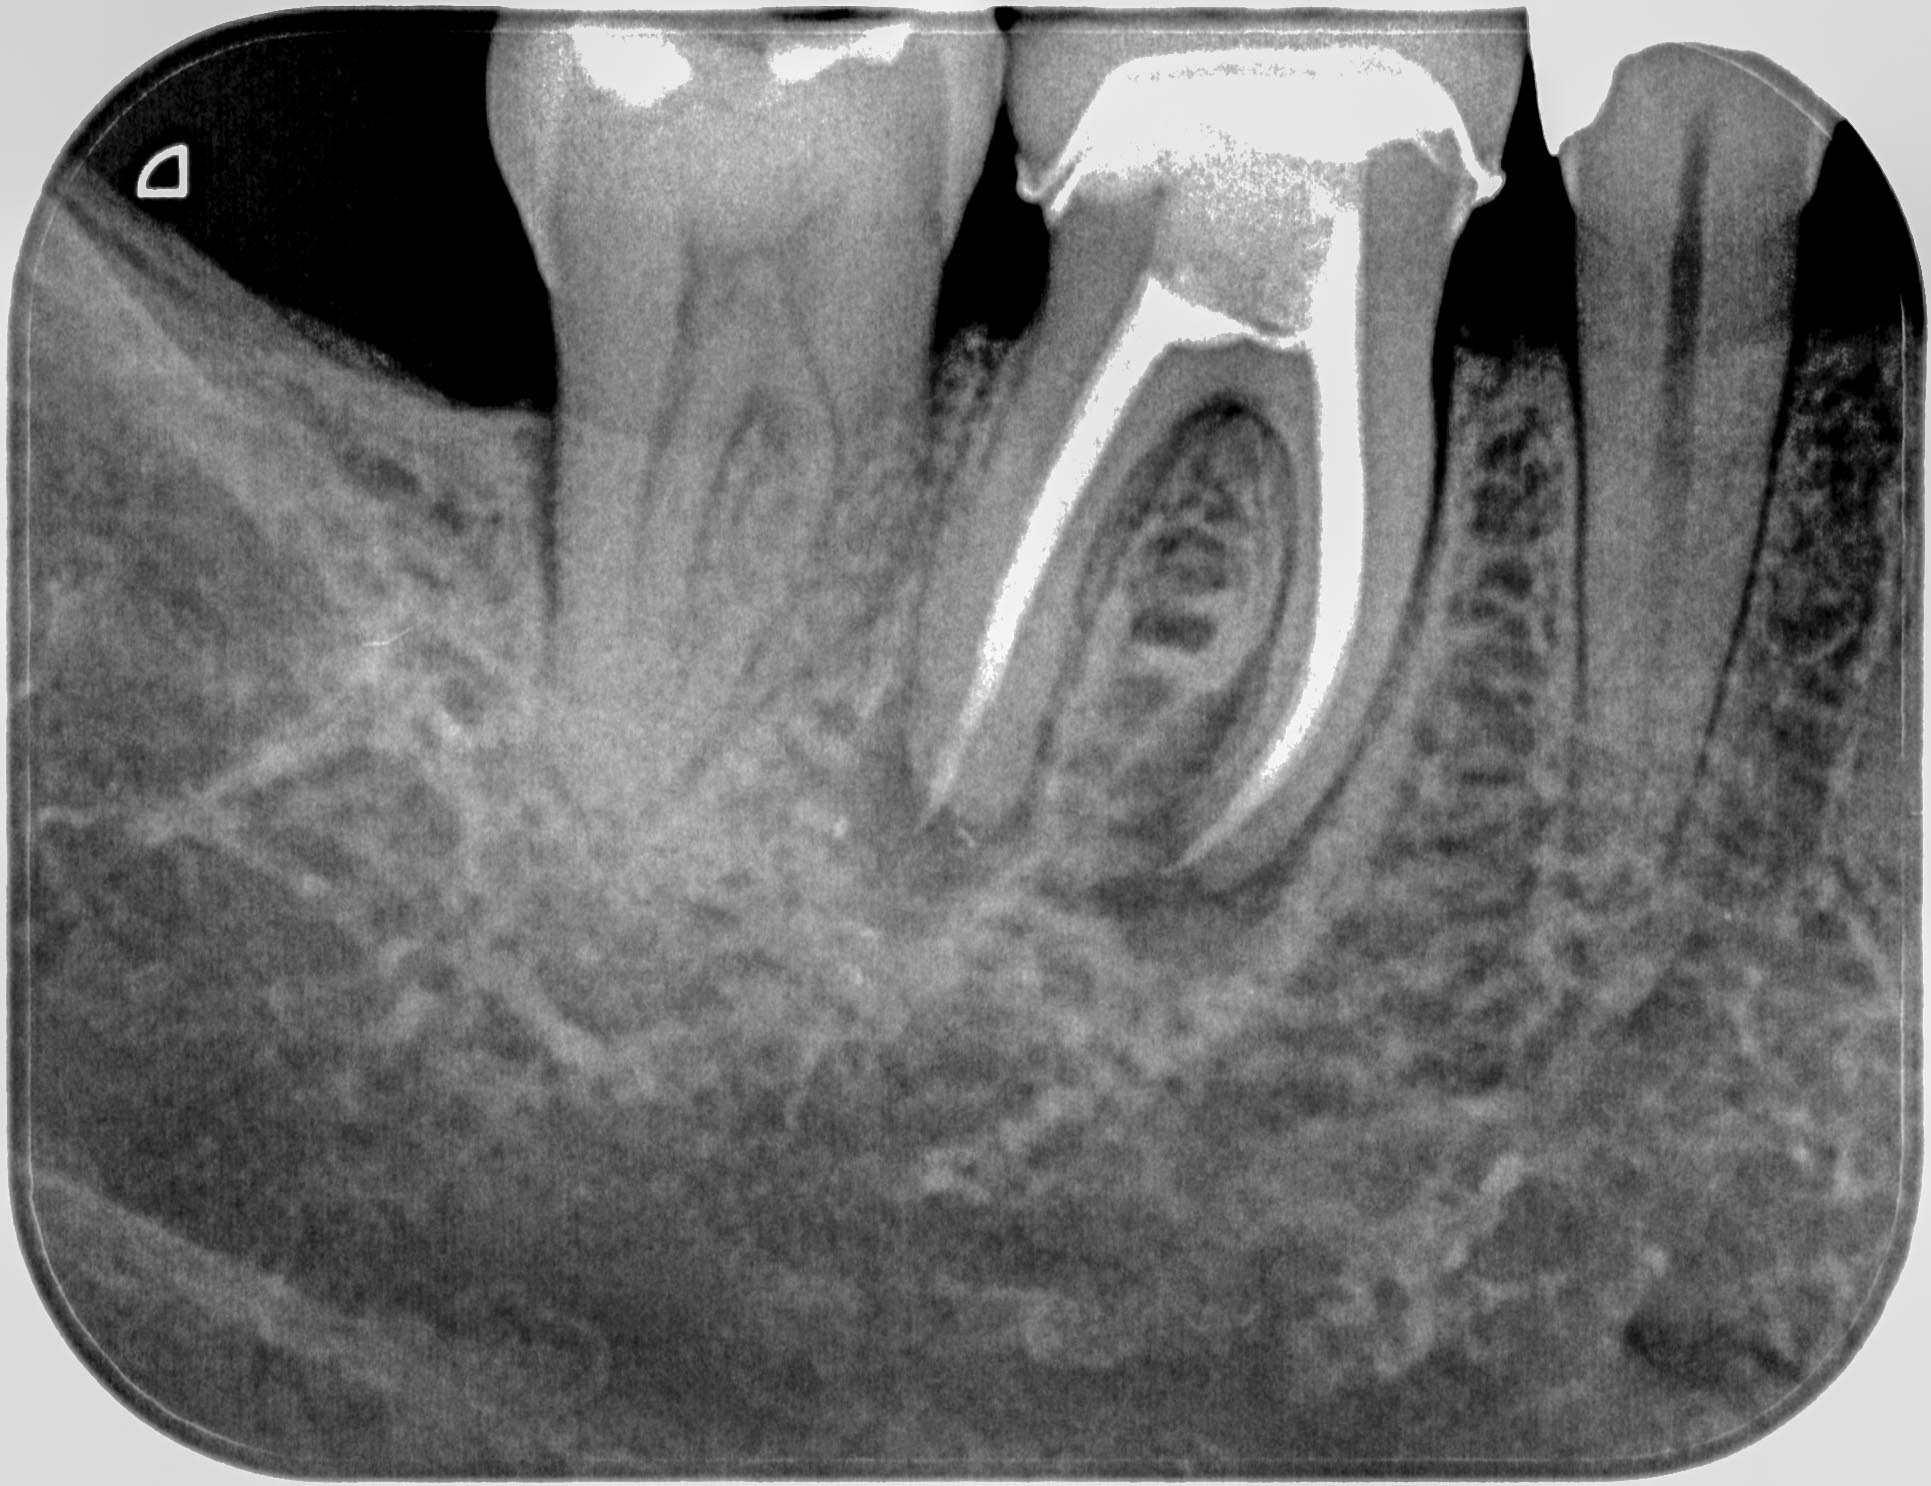

HS46 (1 von 3) Veröffentlicht 21. März 2016 am 1931 × 1486 in Calciumhydroxid- Überpressung (2) 06. November 2015